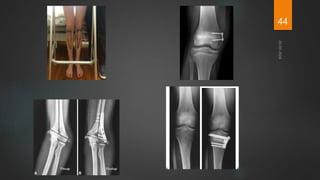

Orthopaedic Treatment

Conservative methods

 Mild deformities correct spontaneously when rickets heals.

 Splints can be used to correct deformities.

Eg- Mermaid splint, Orthopaedic shoes

Surgical Management

 In very young children with deformity, treatment of the metabolic defect

supplemented by bracing/splinting may correct the deformity.

 In prepubertal children or adolescent, medical management and bracing

usually not enough.

 Early osteotomy or growth modulation usually indicated.

 Mobilize as early as possible after corrective surgery.

 Control disease metabolically prior to surgery.

 Stop vitamin D 3 weeks prior to surgery.

 In older children with severe deformity, without past history of medical

management, go for surgery in less homeostatic but metabolically

compensated state instead of loading the patient with vitamin D and

calcium. ( r/o renal osteodystrophy).

 Role of external fixators for correction to be considered.

 In addition to osteotomy, guided growth modulation with

hemiepiphysiodesis has had promising results.